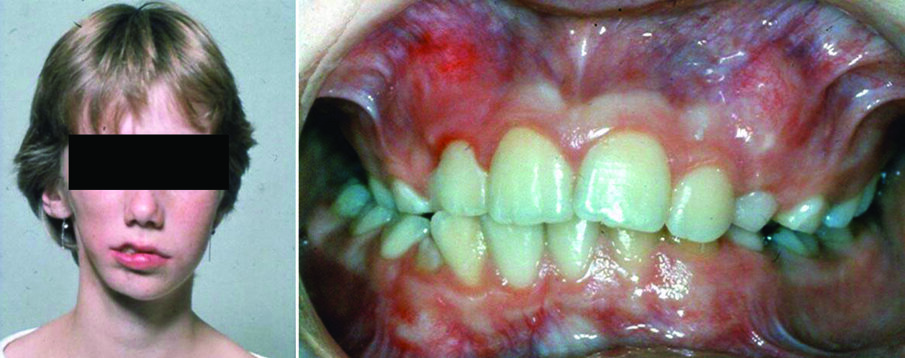

Hemifacial microsomia results from the malformation of the 1st and 2nd branchial arches. Involves mostly unilateral condylar underdevelopment, it may be associated with variable abnormalities of the external and middle ear, has similar manifestations with Goldenhar syndrome, and its etiology is heterogeneous. The extent of TMJ involvement primarily determines severity, prognosis, timing and type of treatment. Face asymmetry in hemifacial microsomia is characterized by chin deviation. Occlusal manifestations include lower dental midline deviation, unilateral cross bite, tilting of the occlusal plane, all of them towards the affected side (Figure 2). Apart from ear abnormalities, soft tissue defects may include skin tags, facial clefts, cranial nerve function, soft palate function, bulk of subcutaneous soft tissue, muscles of mastication and facial expression, macrostomia, and skin tags (3).

Figure 2. Facial photograph of a 13-year-old girl with hemifacial microsomia (right side) (a). The discrepancies include asymmetries in the mandibular body, ramus, and condyle, as well as involvement of the ear. Malocclusion is characterized by right posterior crossbite, tilting of the occlusal plane and lower dental midline deviation to the affected side (b).